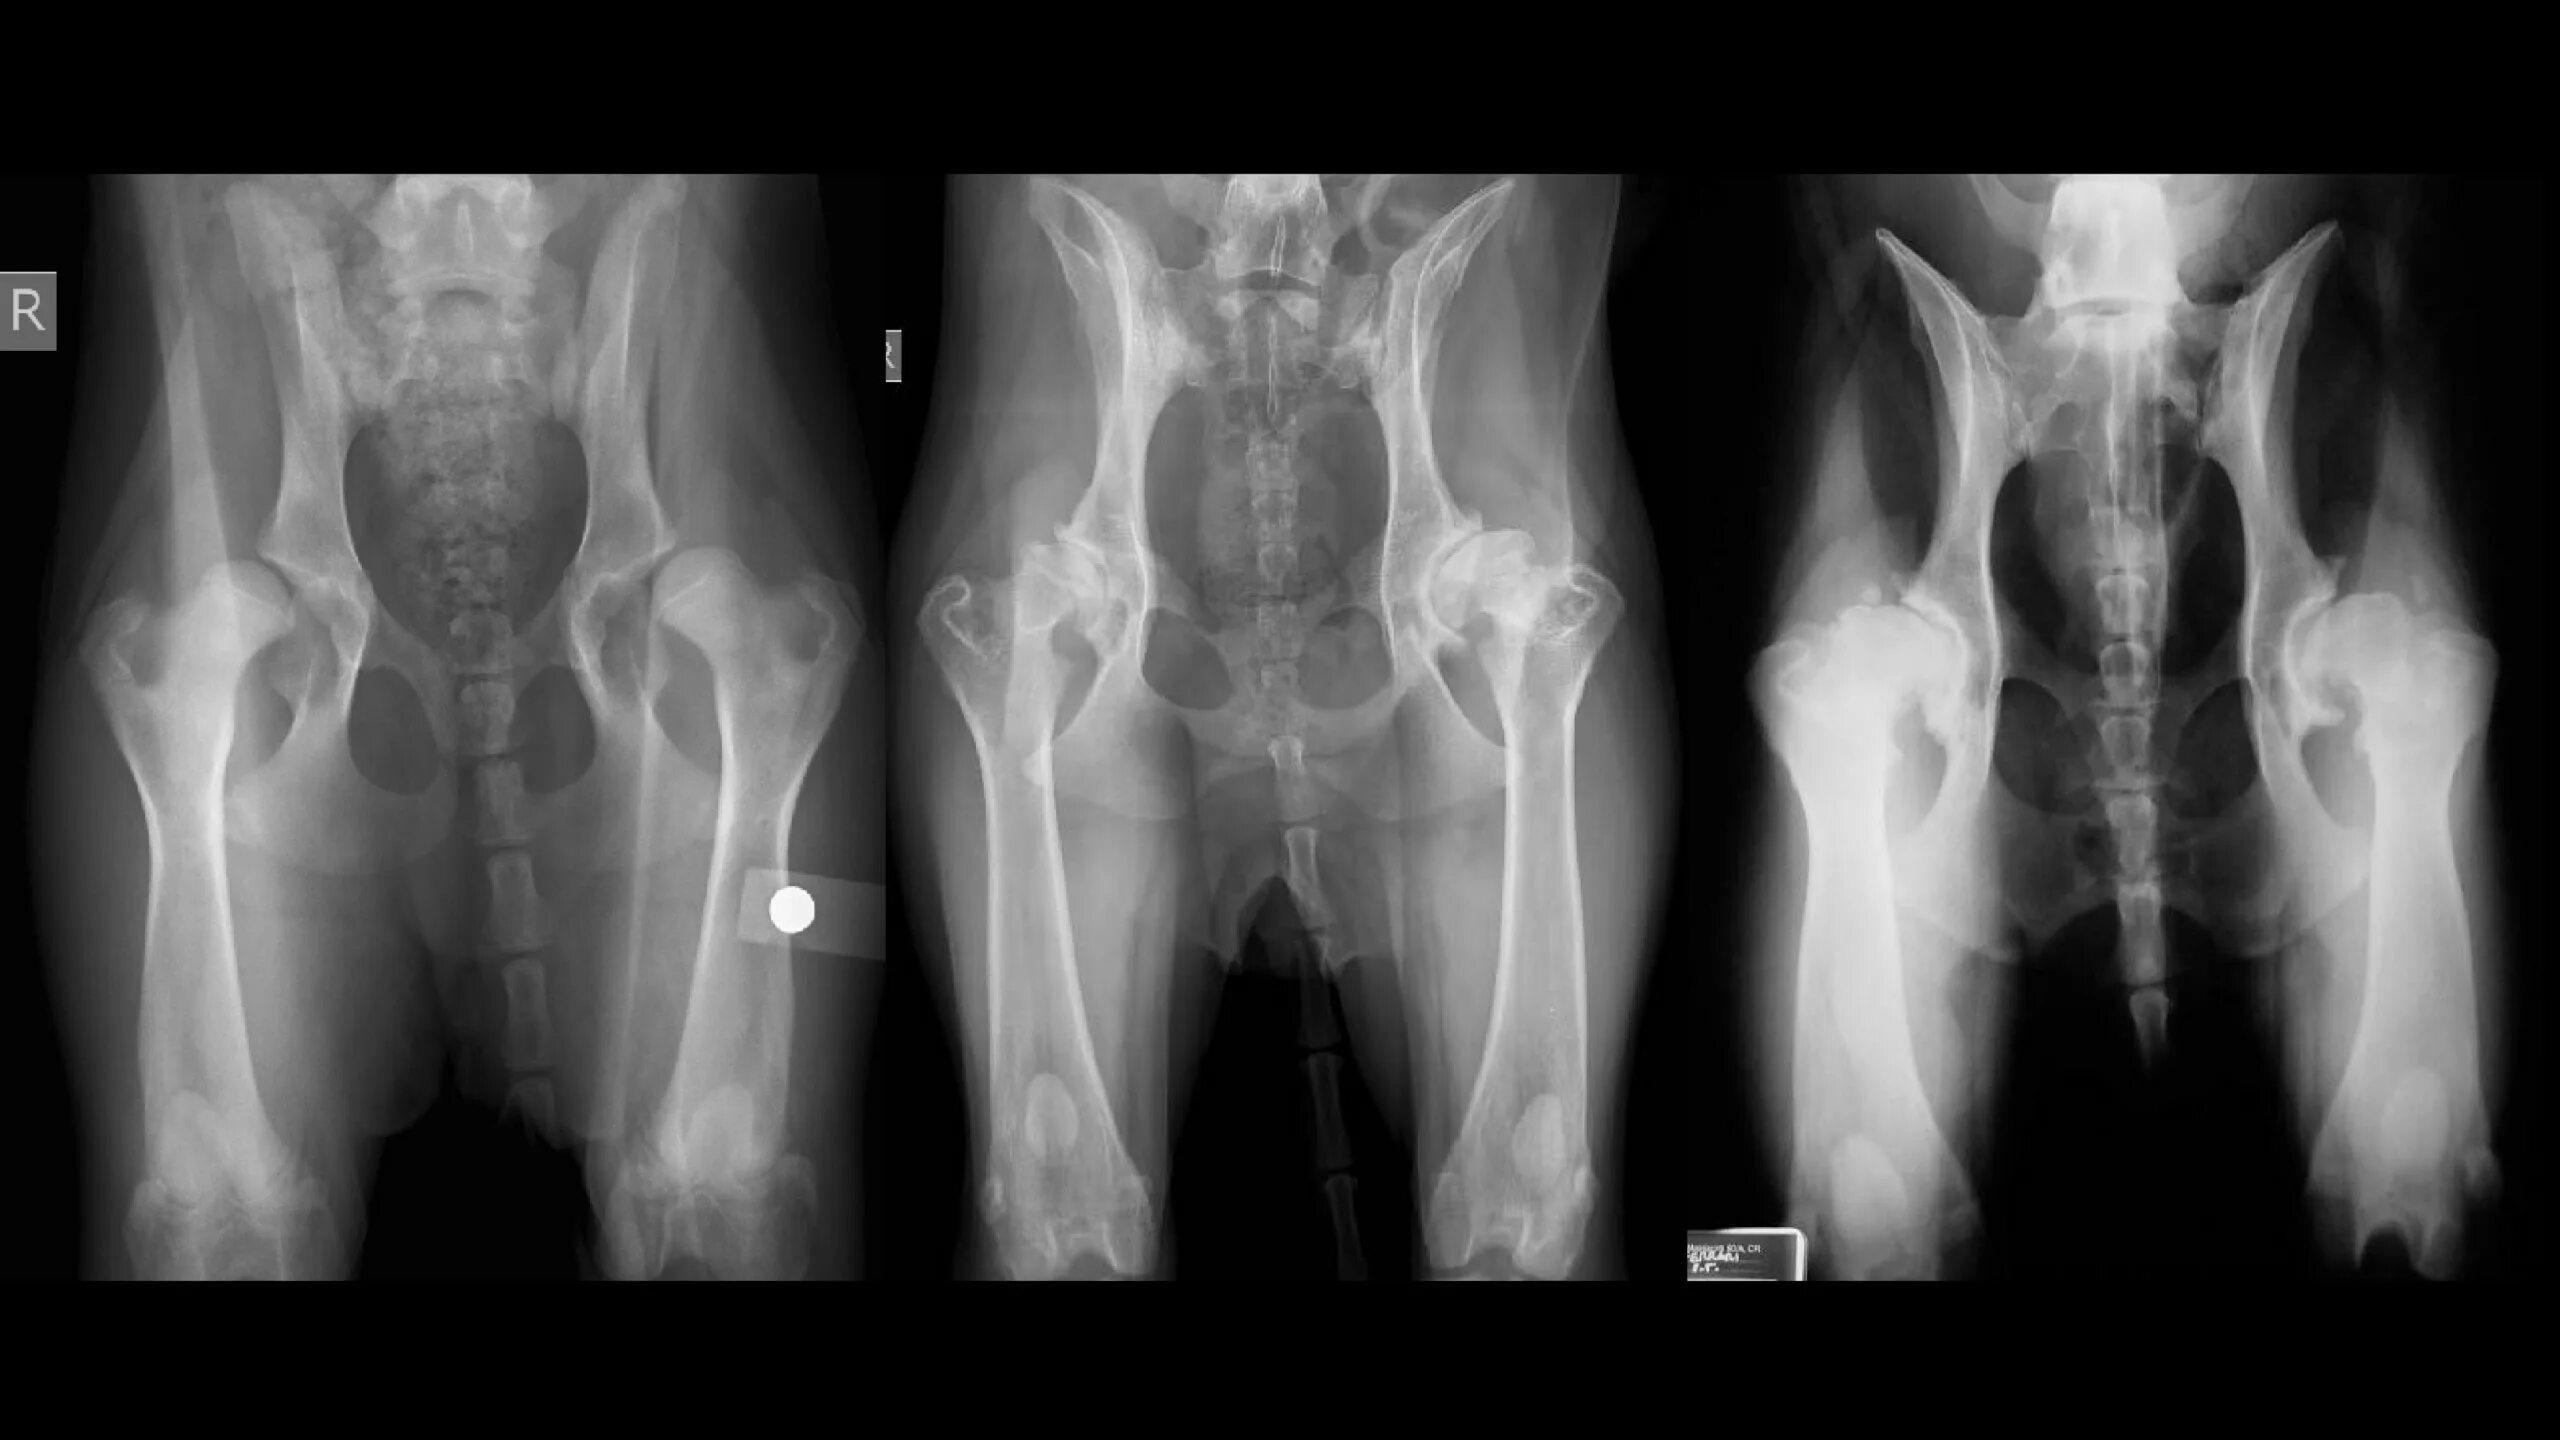

Дисплазия 7 лет